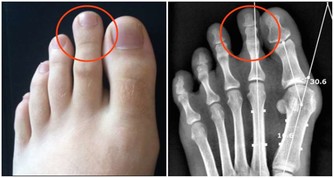

未成年的小孩泡腳每次不可超過10分鐘,水溫不可高過40度。因為小孩的骨頭還未完全定型,若長時間用高溫水泡腳,容易導致腳變成平足。